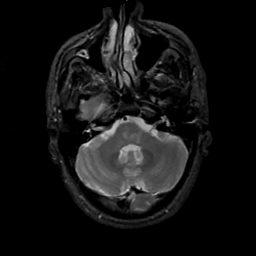

MR Study #2, February 17, 1991 -- Slice #11

[Home][Help][Clinical][Tour 1][Tour 2] Slice 11